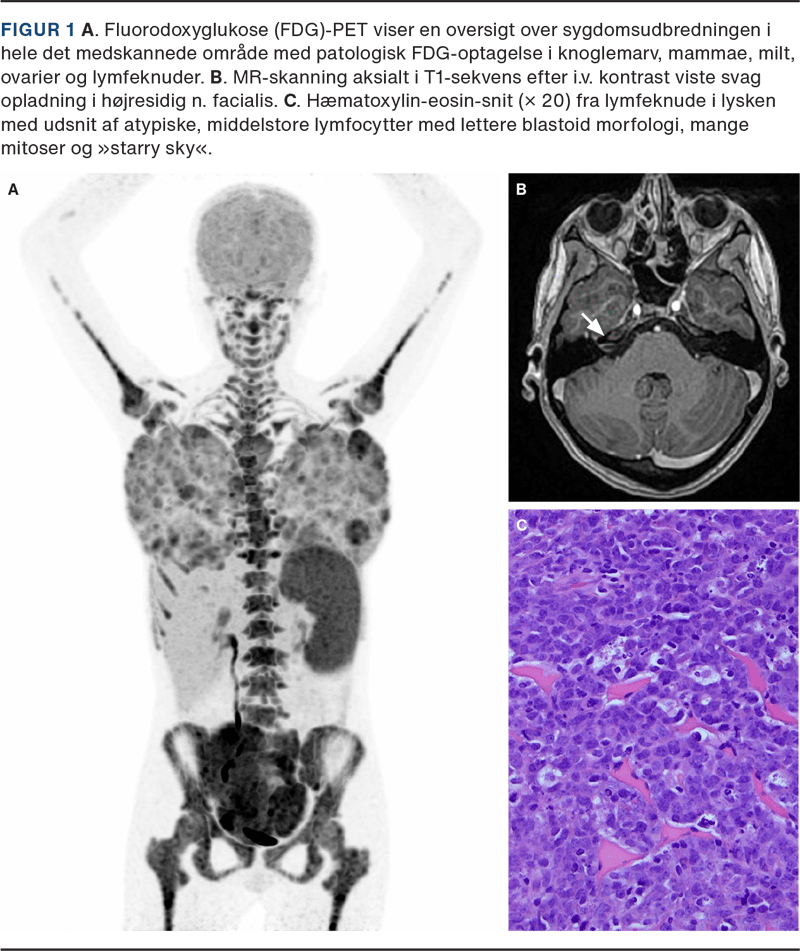

Perifert blodudstryg og flowcytometri, biopsi fra glandler samt PET-CT påviste leukæmiseret BL stadie IV med knoglemarvsinvolvering og ekstranodal affektion i mammae og ovarier (Figur 1 A). En MR-skanning viste let opladning langs højresidig n. facialis (Figur 1 B). Histologiske tests viste klassisk BL med Ki-67 på 100% og MYC-translokation (Figur 1 C).

I en opgørelse af 53 børn med BL havde 19% forbigående perifer facialisparese som led i debutbilledet [4]. Mekanismerne omfatter leptomeningeal spredning eller direkte nerveinvolvering, hvilket understøttes af den beskedne MR-opladning langs n. facialis hos vores patient [2].

Mammaeaffektion er sjælden ved sporadisk BL og typisk sekundært til dissemineret sygdom. Hos piger og unge kvinder kan det hormonelt aktive og vaskulariserede mammavæv være særligt modtageligt for lymfocytinfiltration, men væksten skal fortsat forstås i lyset af BL’s i forvejen ekstremt høje proliferationsrate [3].